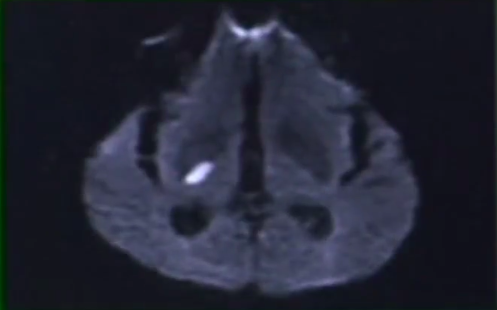

Qual o exame padrão ouro para detectar isquemia cerebral ?

Sequência de difusão na RNM (edema intracelular por conta da perda da bomba de Na e K)

O que um vaso hiperdenso representa na TC?

Trombo no interior do vaso (aparece com poucas horas de evolução)